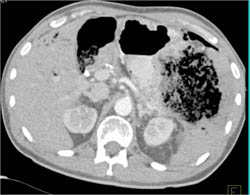

Antral Carcinoma